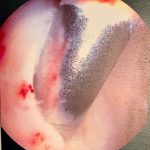

Surgical pictures

Large bone spur

1 cm tear in supraspinatus

You can see from the bone spur outlined in red above that my tear was an caused by repetitive micro trauma over time. Eventually, the tendon became tattered and torn. All the years of weight training probably contributed to some of this, as well as my type 2 acromion. I ended up with three total anchors and a suture bridge repair.